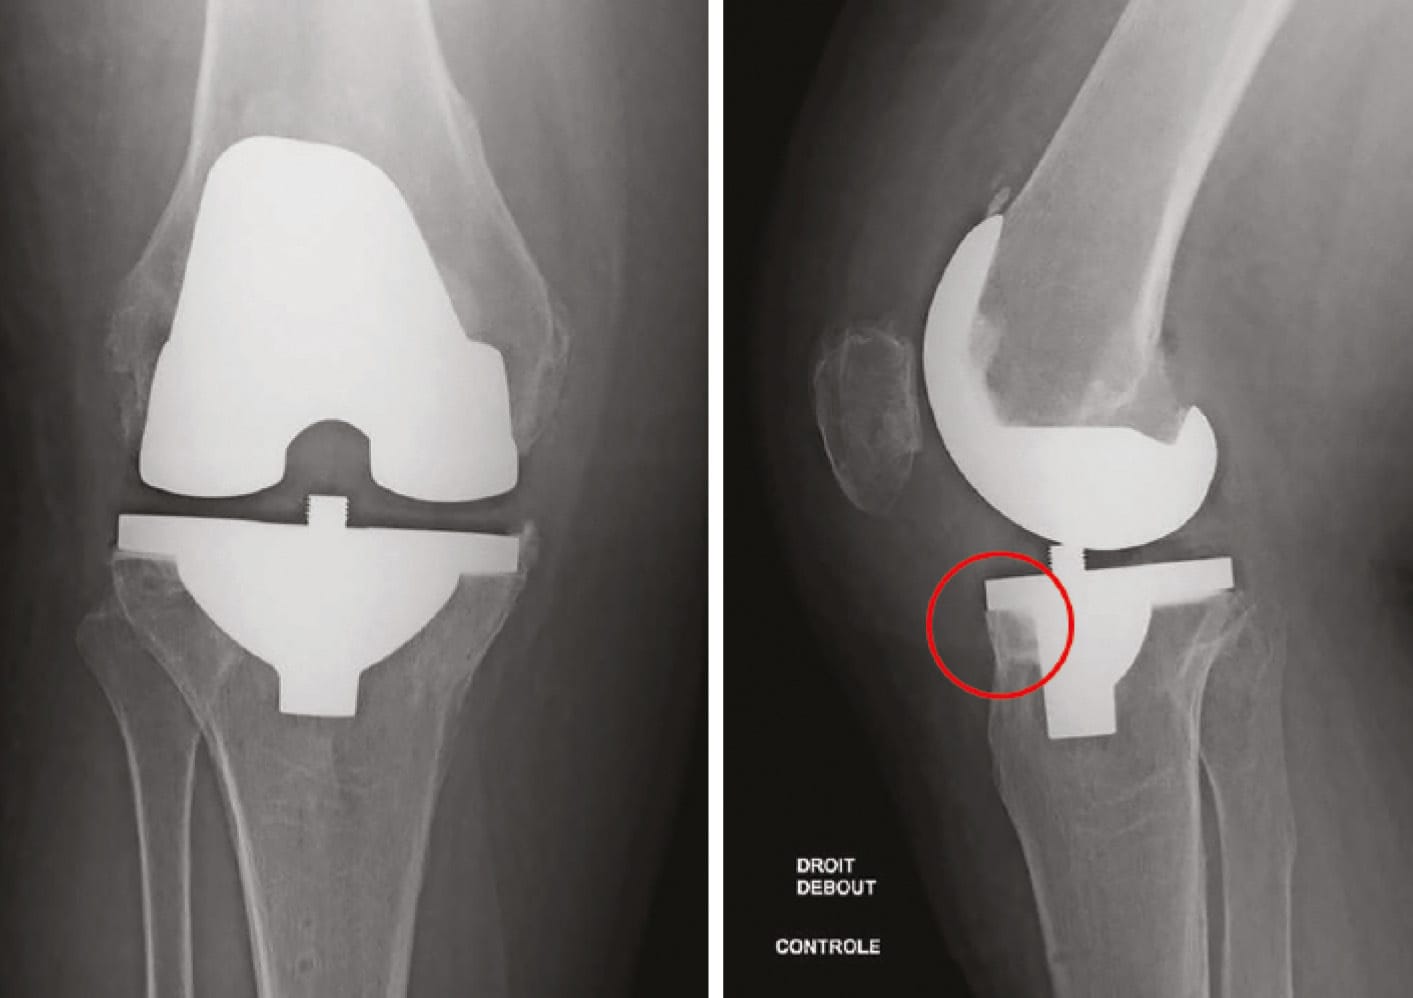

Treatment of substantial valgus deformities was facilitated by use of the lateral subvastus route with better analysis of medial stability. Management of genu varum was conducted within the joint casing without applying medial release, though that would have been possible even using the lateral subvastus route (Figure 10 ).

During the transition period, when appointments for patients undergoing surgery 3 months previously via the medial route coincided with those for patients undergoing surgery 1 month earlier via the lateral subvastus route (Figures 11 & 12), we realized that convalescence had been reduced by 2 months. A multi-centre study comparing the two types of approach is currently under way.

The functional scores are identical but the side on which the lateral, minimally invasive route was used is more comfortable. Radiographic assessment demonstrates that patellar alignment is always perfect with the lateral subvastus route.